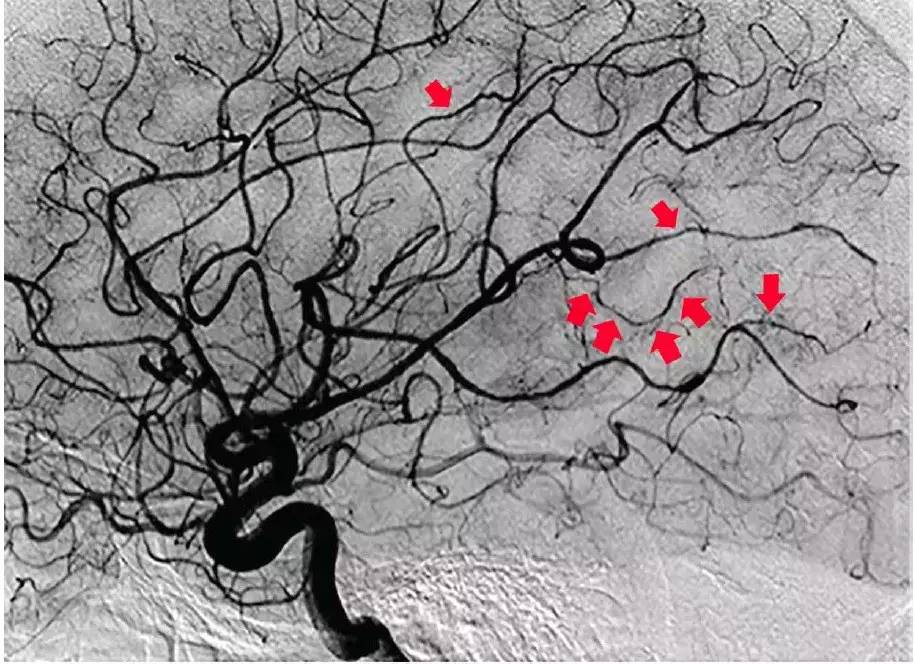

下图DSA显示多支动脉远端变窄和不规则。